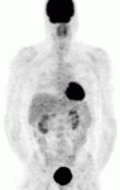

MIBG Scintigraphy – the pheochromocytoma is appreciated in the left panel on the right side of the screen (right panel; left side of the screen) as the darkened circle towards the abdomen. The darkened structure at the head of the patient is the thyroid gland, while the darkened structure in the pelvis of the patient is the bladder. This is normal physiologic uptake.

The first functional imaging technique utilized in pheochromocytoma patients was 123I-MIBG scintigraphy (Image Right). Given the compounds similar structure to the catecholamine norepinephrine (secreted by pheochromocytomas), MIBG was well-suited for uptake by most neuroendocrine tumors.[83] Furthermore, if a patient was found to be positive on an MIBG scan, they were eligible for MIBG treatment, offering additional avenues for those suffering from widespread metastatic disease.[84] However, further investigation revealed that while MIBG excelled with adrenal lesions, it was far less superior in patients with extra-adrenal paragangliomas, particularly with specific genetic variants like succinate dehydrogenase subunit X (SDHx).[72] As the positron emission tomography scans were developed, MIBG has slowly loss its favor for the pheochromocytoma patient.[72]